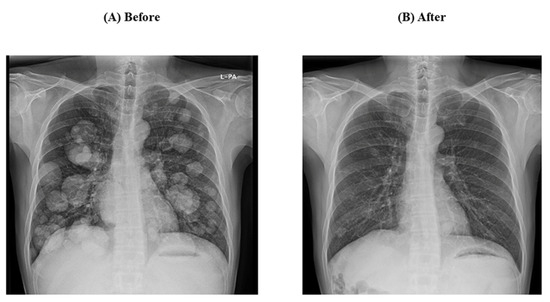

- Case 1

- Case 2